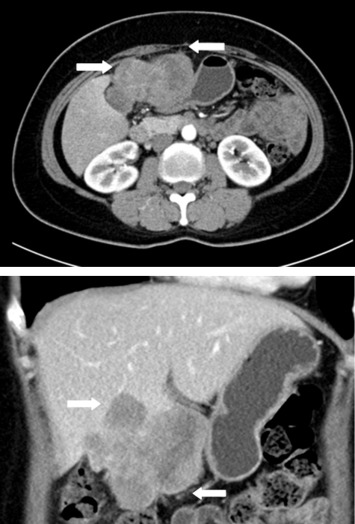

A 52-year-old female patient presented with postprandial epigastric pain that had persisted for 1 year. The pain was mild and improved after antacid treatment. She was seen at our hospital after being diagnosed with a hepatic tumor at a local clinic. Abdominal ultrasonography revealed one mixed echogenic tumor approximately 9.5 cm from the gallbladder sac and extending to S4–5 of the liver. The common bile duct was dilated to 1.4 cm (Fig. 1). Liver function tests and total bilirubin levels were within the normal range. However, carbohydrate antigen 19-9 (CA 19-9) was elevated to 60.9 U/mL. A follow-up abdominal computed tomography (CT) confirmed a 7.5 cm sized gallbladder cancer with liver invasion (Fig. 2), consistent with clinical Stage III cancer according to the TNM system (tumor-node-metastasis classification system).

Abdominal computed tomography confirmed a 7.5 cm gallbladder cancer with liver ...

Figure 2.

Abdominal computed tomography confirmed a 7.5 cm gallbladder cancer with liver invasion.